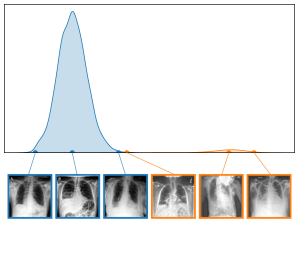

Alternatively, inspired by RelMax, we can compute bias scores using relevance scores instead of activations, as outlined in Appendix A.2. Since relevance scores are computed class-specifically, this approach allows distinguishing concepts that are artifactual for certain classes but valid for others. An illustration is provided in Fig. 2 (left), where a CAV has been trained to distinguish between known artifact () and non-artifact samples (). This concept representation can subsequently be used to compute concept scores for unknown samples (), supporting annotators in the detection of further artifact samples.

Both input and latent relevance clustering require subsequent human supervision to determine whether outlier clusters represent valid or spurious behavior. To semi-automate this process, Anders et al. [3] propose using Fisher Discriminant Analysis [37] to rank class-wise clusterings by linear separability, while Dreyer et al. [27] computes similarities between prototypes. The results of clustering approaches can serve as an initial set for bias modeling methods outlined in Sec. 3.2, which can be refined iteratively. An example outlier cluster of latent relevances is shown in Fig. 4 (top), with all samples containing the spurious band-aid concept.

We further plot the distribution of CAV-based bias scores for biased and clean samples for the real-world artifacts ruler (ISIC2019) and pacemaker (CheXpert) in Fig. 8. We compute bias scores using the best performing CAV per artifact and use latent activations after the residual block of the ResNet50 model for ruler, and the convolutional layer of the VGG16 model for pacemaker. We show samples corresponding to the bias score in the top-1 and -99 percentiles of each set. Samples near the decision boundary are particularly interesting, as they may arise from labeling errors. Both examples demonstrate the retrieval of unlabeled artifact samples. The distributions of bias scores for additional artifacts are shown in Appendix A.6.2.